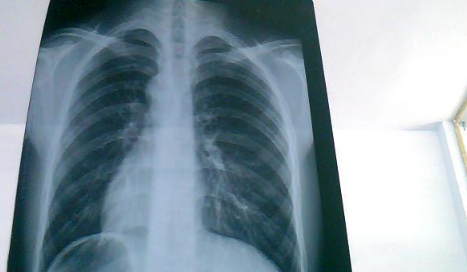

如果出现白肺,患者可能会出现一些严重的呼吸道症状,包括咳嗽、喘息、呼吸困难或体力活动时呼吸短促。一个更客观的指标是病人的呼吸频率,通常大于每分钟30次呼吸,或血氧饱和度低于93%就要警惕出现严重肺部感染。白肺并不能预防,只能预警。

肺白了一般是指白肺,白肺能否恢复与疾病类型、严重程度有一定关系,有些患者在检查时,发现肺白密度增高,如果是轻度肺部炎症引起的白肺一般是可以恢复的,如果是严重肺部炎症或肺间质纤维化引起的,则可能无法恢复。